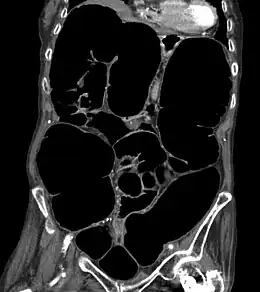

Description de l'image Ogilvie ct coronal.jpg.

Le scanner abdomino-pelvien avec injection de produit de contraste iodé est l'examen de référence[4] : il montrera des signes pathognomoniques d'occlusion intestinale (niveaux hydro-aériques, dilatation des anses intestinales) sans zone de transition et en l'absence d'obstacle obstruant la lumière intestinale.